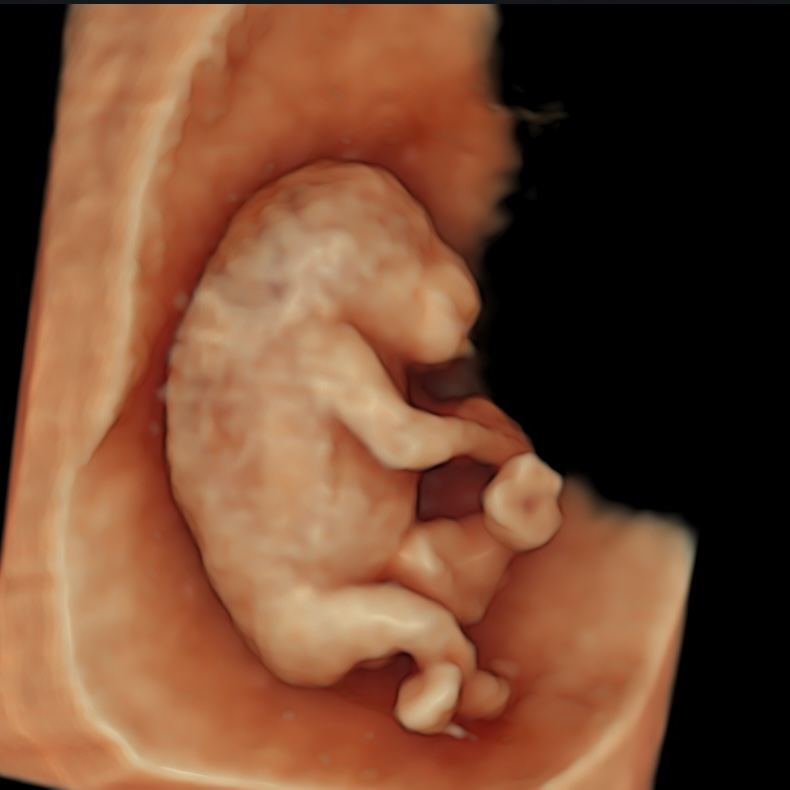

Combining the earliest structural screening for most severe anomalies with precise NT measurement in a single scan

At this early stage the baby is very small, so the scan is usually done through the vagina (transvaginal) to get the sharpest images. The transvaginal probe sits closer and uses higher-frequency sound, giving better resolution for tiny structures including the NT.

We can scan through the tummy (transabdominal) if the view is good, but detail is often lower because the beam travels further and is partly absorbed by the abdominal wall; we’ll use whichever gives the best view—both are safe.

We scan first to confirm NIPT is appropriate. Several early major anomalies like acrania, amniotic band syndrome, body-stalk anomaly, cloacal exstrophy, limb–body–wall complex, pentalogy of Cantrell, and sirenomelia, are usually non-genetic with a very poor prognosis.